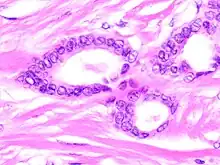

Tubular carcinoma is a subtype of invasive ductal carcinoma of the breast.[2][3] More rarely, tubular carcinomas may arise in the pancreas[4] or kidney.[5] Most tubular carcinomas begin in the milk duct of the breast and spread to healthy tissue around it.[6][7]

Tubular carcinomas are generally around 1 cm. or smaller, and are made up of tubules. They are usually low-grade.[2] Elastosis has been noted as common but is not present in all cases.[11]

- 1 2 Stavros, A. Thomas (2004). Rapp, Cynthia L.; Parker, Steve H. (eds.). Breast Ultrasound. Lippincott Williams & Wilkins. pp. 647–649. ISBN 978-0-397-51624-7. OCLC 1065689596. p. 649:

A highly differentiated invasive carcinoma that forms well-defined tubules (containing epithelium, but no myoepithelium) and that have abundant desmoplastic fibrous stromal reaction between the tubules.